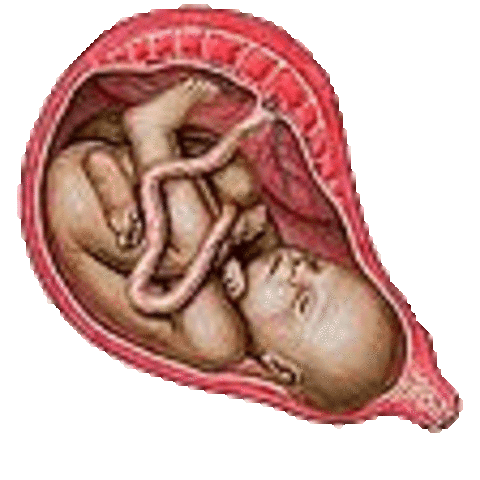

• week 40

week 40

•You have now reached the time of delivery.

•All systems are developed and ready to go.

•Now it is just a matter of time.

•Baby is about 20 inches (51cm) and weighs approximately 7.5 pounds (3.5 kg).

•The head has a diameter of about 4 inches (10 cm).

•The contractions could begin at any moment.